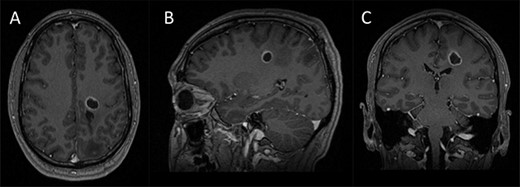

Preoperative imaging; (A–C) axial, sagittal and coronal T1-wieghted magnetic resonance imaging (MRI) images, with gadolinium demonstrating a contrast enhancing lesion in the left corona radiata.

A 42-year-old, right-handed gentleman presented with 1-month history of right foot weakness and focal seizures. Imaging revealed a 1.6 × 1.4 × 1.6 cm enhancing lesion in the left corona radiate (Fig. 1). He underwent stereotactic frameless needle biopsy using the method previously described by our group [6]. The biopsy result was inconclusive, the procedure was uneventful and he recovered without neurological deficit. Post-operative computed tomography (CT) showed the biopsy site was posterolateral to the lesion and following discussion in our neuro-oncology multidisciplinary team meeting the consensus was to perform an open biopsy.